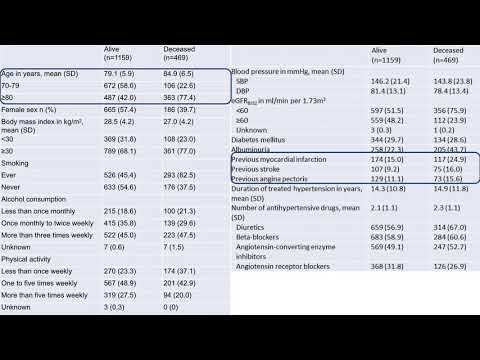

Caracteristicas basales y perfiles de riesgo de los participantes del estudio ISCHEMIA. Dra. Carolina G. Reynoso. Residencia de Cardiología. Hospital C. Argerich. Buenos Aires